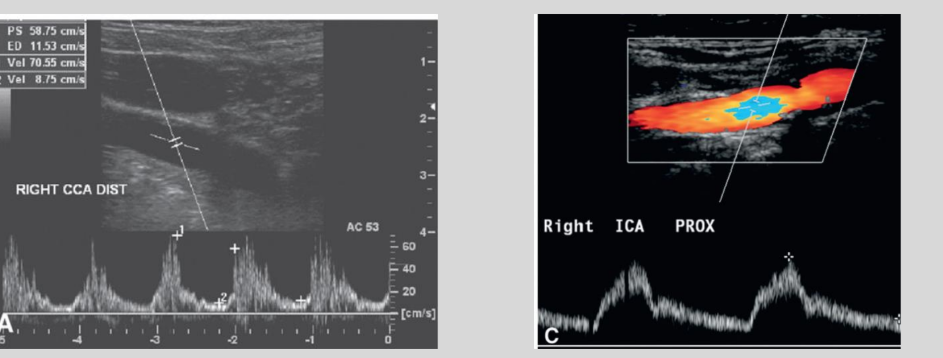

◦ Aortic Valve Stenosis

Typically, will be diagnosed prior to ultrasound

◦ Dampened waveform in bilateral carotid system

◦ Overall lower velocities

◦ Use velocity ratio

what waveform is this

Aortic Valve Stenosis